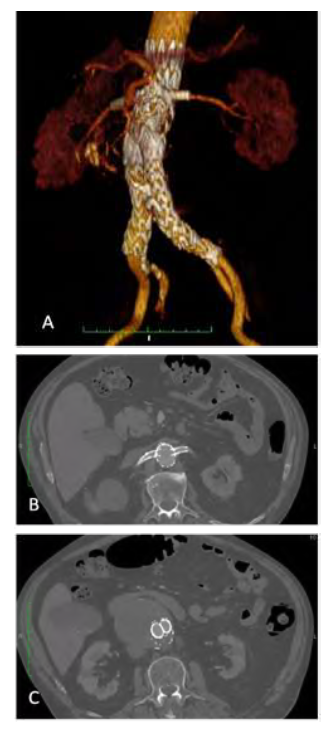

The final completion angiogram demonstrated perfusion of bilateral renal arteries, resolution of the Ia endoleak and without further endoleaks, as well as perfusion of both hypogastric arteries (Figure 5). At two months of follow-up, the patient remains asymptomatic and the angio-CT scan showed resolution of type Ia endoleak (figure 6) and the presence of a late type II endoleak.

Fig 6: Two-month post-operative follow-up CTA. A: Three-dimensional reconstruction of the Fenestrated Stent Graft with patent stents and resolution of type Ia endoleak; B: axial fenestrated stent graft at the level of the renal stents; C: Kissing aortic covered stents in parallel graft configuration)